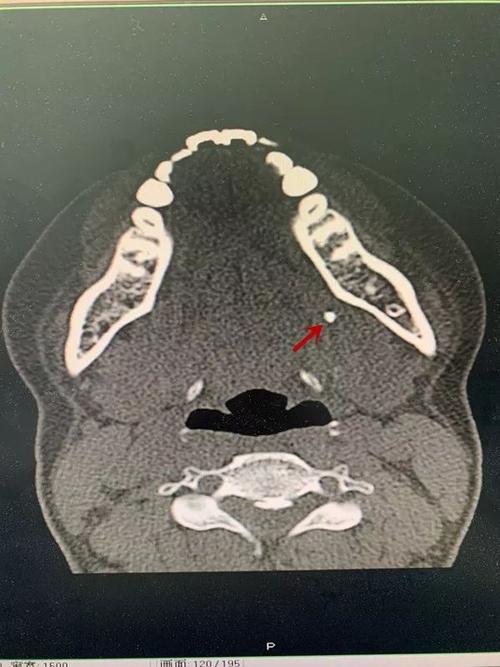

刘某,男,36岁,右侧颌下腺导管结石,ct片可见右侧口底前份,以及靠近

颌下腺导管结石ct图片